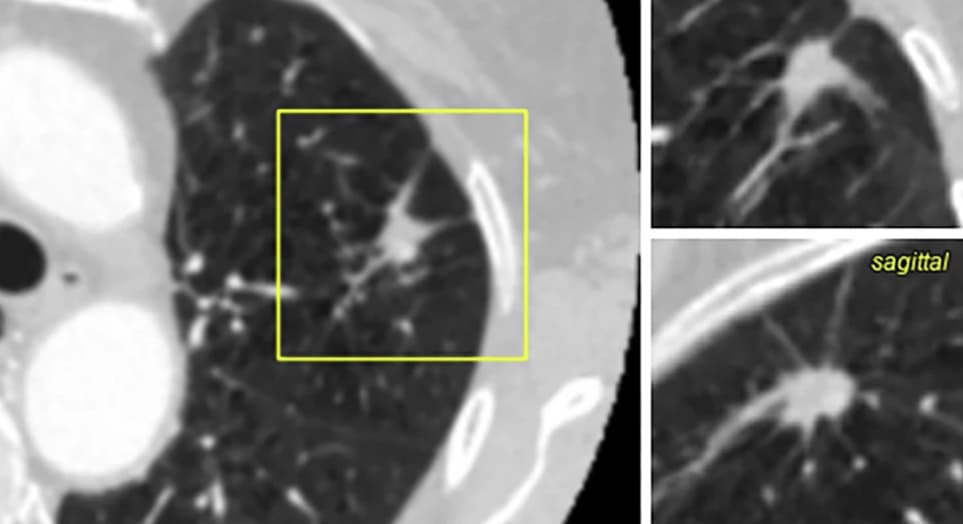

Une classification des nodules pulmonaires est classiquement réalisée à partir du modèle de Brock afin de réduire le nombre d’examens pour classer les nodules pulmonaires en TDM. Une étude publiée dans la Revue European Radiology compare les résultats obtenus par un modèle de deep learning à ceux du...